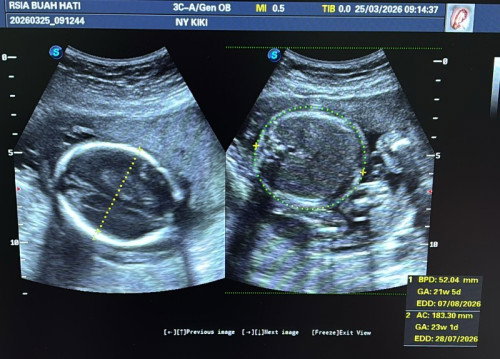

23w air ketuban berkurang, setalah dr diagnosa bgtu jjr langsung blank bingung mau nanya apa lagi dan apa yang di omong sm dr jadi ga ngerti. Disini ada ga yang punya pengalaman kaya saya ? Jujur seminggu akhir2 masa puasa saya di kampung jarang bgt minum air putih, sllu minum es kopi karna cuaca di kmpng bnr2 puanas poll. Dan perjalanan saya lumayan jauh 7 jam naik motor itupun banyak berhenti2 nya. Setelah dri kampung pas di usg dr bilang air ketuban nya Pas2an tapi di note nya air ketuban berkurang. Hasil cek darah nya juga HB saya 9,9. Saya tanya apa saya kurang minum air putih, dr bilang ngak juga. Akhir nya sya di resepkan obat antibiotik, D3, kalsium. Vit yang biasa saya konsumsi Folamil Genio biasanya saya minum 1 skrng di suruh minum 2. Jujur worry bgt bun, apakah bahaya atau gumana ? #mohonbantujawabbunda